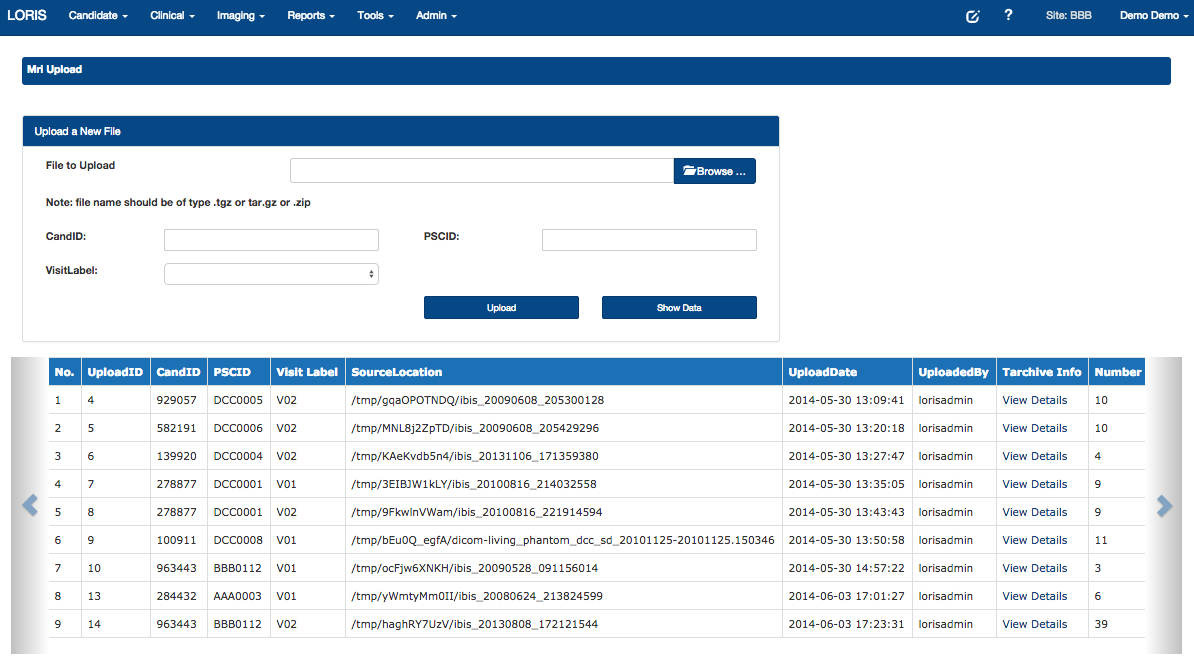

Imaging Uploader - New